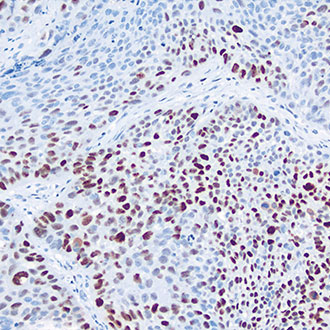

IHC

免疫组织化学(IHC)